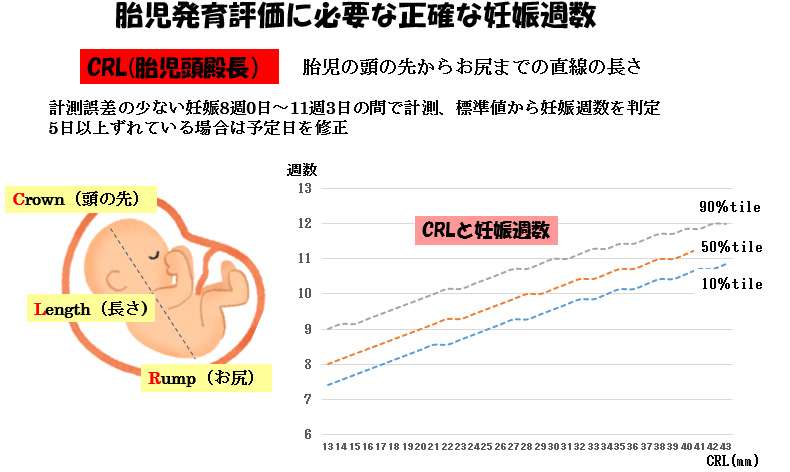

医師監修 胎児の発育曲線 成長曲線 とは?どのように見ればいいの?ゼクシィBaby。

胎児発育曲線』とは?週ごとの発育の目安を助産師が解説◎ - 株式会社エバーセンス。

胎児発育曲線』とは?週ごとの発育の目安を助産師が解説◎ - 株式会社エバーセンス。

胎児発育曲線の±2.0SDの意味は?エコー写真に学ぶ統計学 - 日常を少し掘り下げてみる。

医師監修 おなかの赤ちゃんの発育は順調? 「胎児発育曲線」とはトモニテ。

胎児発育曲線の±2.0SDの意味は?エコー写真に学ぶ統計学 - 日常を少し掘り下げてみる。